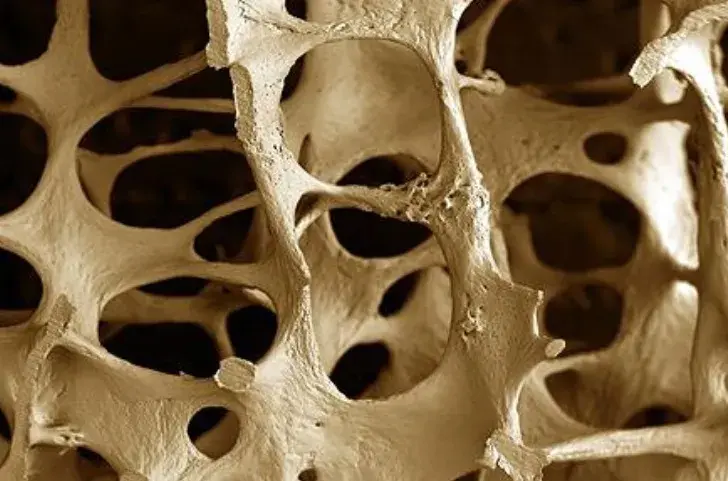

Injúria Renal Aguda (revisão Lancet 2025)

Injúria Renal Aguda (revisão Lancet 2025)